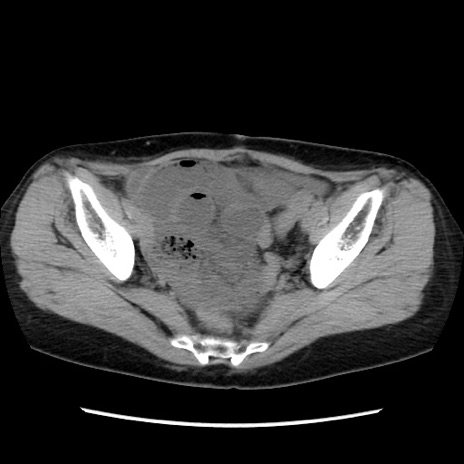

症例32(横断像)

【症例】40歳代 女性

【主訴】上腹部痛、嘔気・嘔吐

【現病歴】約9時間前頃から急に上腹部痛、嘔気、嘔吐が出現。改善しないため救急要請。

【既往歴】子宮頚癌(広汎子宮全摘術、放射線療法)、腸閉塞

【身体所見】腹部:平坦、軟、腸雑音亢進、上腹部を中心に腹部全体に圧痛あり。

【データ】WBC 8400、CRP 0.03